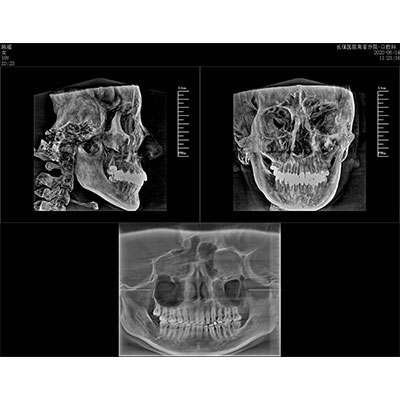

高清口腔三維CT/全景影像 PLX3000A

該款牙科CBCT產(chǎn)品采用動態(tài)平板探測器,獲得三維圖像的同時還具有數(shù)字化全景功能,廣泛應(yīng)用于口腔頜面外科、正畸科、正頜外科、種植科、牙體科、顳下頜關(guān)節(jié)科等術(shù)前術(shù)后。

專有三維重建算法,可提供任意位置高清斷層影像。

通過三維容積影像,提取高清口腔全景影像。

可同時觀察軸向面、冠狀面和矢狀面圖像,方便臨床診斷。